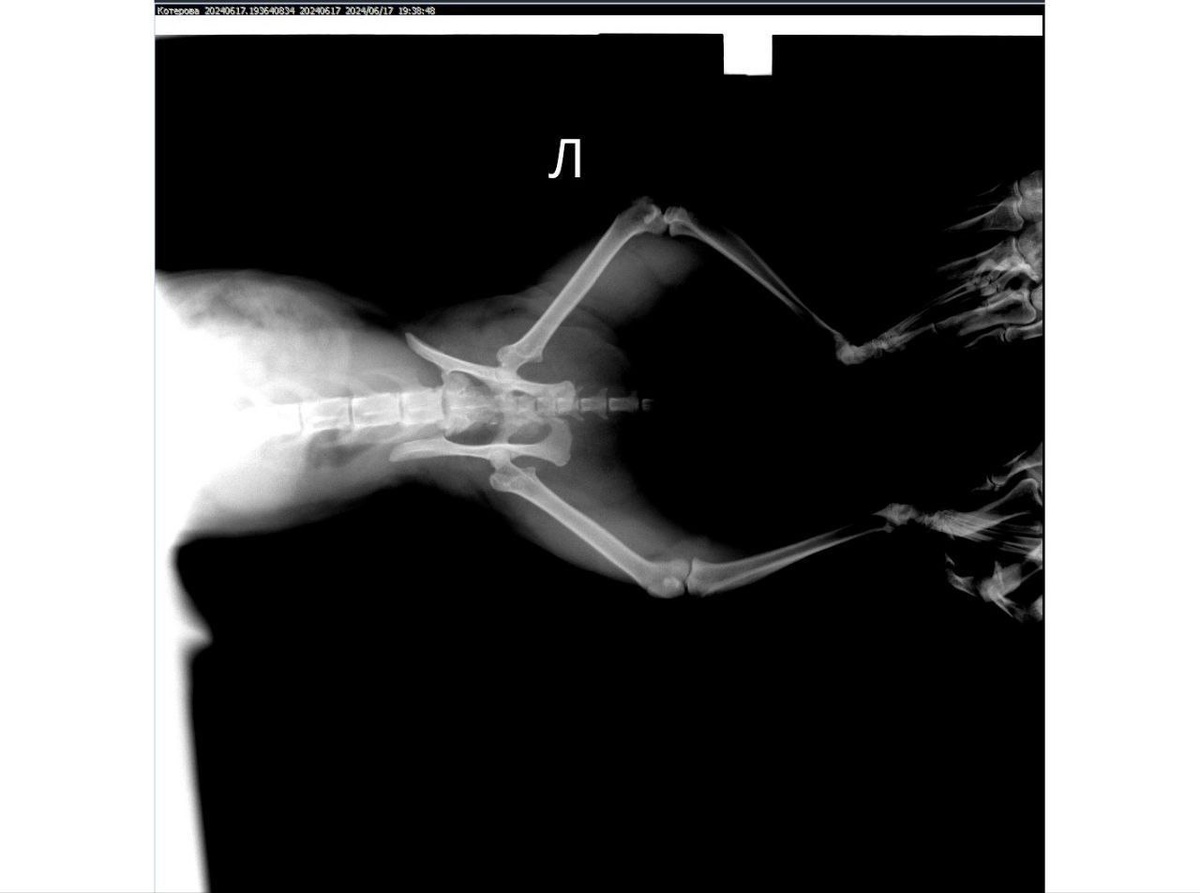

Бездомная кошечка была сбита автомобилем в Бердянске, и найдена неравнодушными жителями. Как оказалось, после встречи с автомобилем, у животного был перебит позвоночник. Даже обезболивающие не помогали бедной кошечке справиться с жуткими болями. Помочь несчастной вызвались волонтеры из Донецка – уже хорошо известный жителям ДНР «Кошкин Дом», который спасает животных с линии боевого соприкосновения и из освобожденных населенных пунктов по всей линии фронта.

Снимок позвоночника кошки. Фото: ТГ-канал «Кошкин Дом»